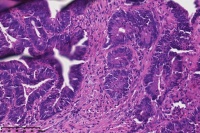

中分化腺癌?

性别

女

年龄

67岁

临床诊断

一般病史

直肠占位

标本名称

大体所见

腺癌(低一中 分化)

中分化腺癌